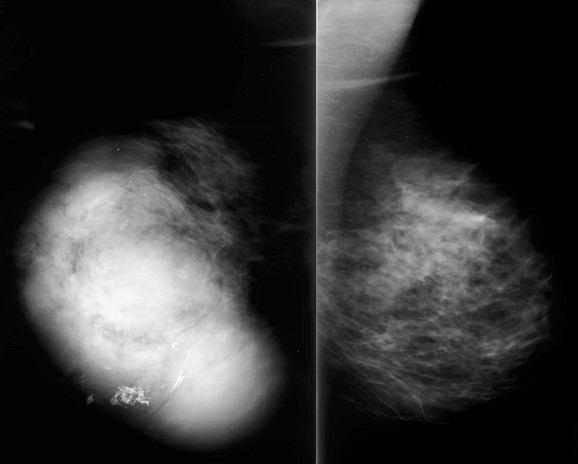

When the tumor is very large, the breast affected with ILC can appear to be getting smaller on mammography—the “shrinking breast” (Fig. 11-3). This is not due to the breast becoming physically smaller, but to the decreased compressibility of the breast tissue that is full of webs of cancer cells. If the contralateral breast compresses to a thickness of 5 cm, a breast with extensive ILC may only compress to 8 cm. Although this results in the appearance of a smaller breast on mammography, breast size is typically symmetric on clinical examination.

FIGURE 11-3 Shrinking Breast.

A 52-year-old woman noted thickening in her left breast. On clinical examination, the breasts are symmetric in size but the texture of the left breast is diffusely thickened. On mammography, the left breast appears to be smaller than the right. Biopsy showed ILC. Did you also notice the one-view asymmetry in the right medial breast? US of this area shows a small hypoechoic mass. Biopsy of the right breast showed IDC.

On US, ILC may present as a defined mass (see Fig. 11-3) but more often presents as ill-defined areas of shadowing without a distinct mass (see Fig. 11-2). The lines and arcs of tumor can produce bands of shadowing, like the edges of a spider web. Although tumor size is often underestimated by US, this modality is more accurate than clinical examination or mammography in assessing extent of disease.